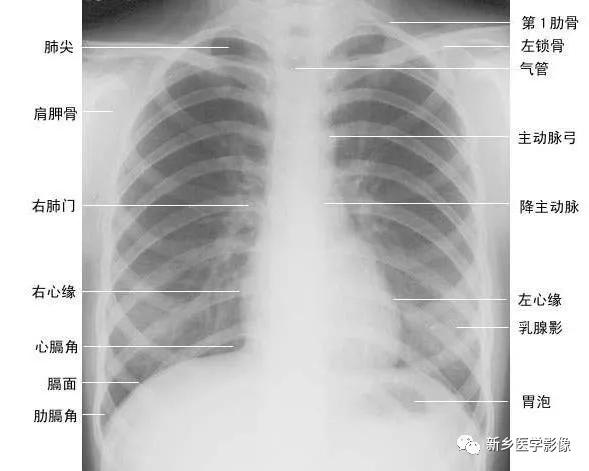

正常胸廓由软组织与骨骼组成,两侧对称(如下图)。

(一)软组织 1、胸锁乳突肌及锁骨上皮肤皱褶 胸锁乳突肌起自胸骨柄及锁骨内端,向后上方斜行,止于乳突,在两肺尖内侧形成外缘锐利且较均匀的致密阴影。在胸骨头和锁骨头及锁骨之间形成一个小三角间隙,叫锁骨上窝或胸锁乳突肌间隙。当颈部偏斜时,两侧胸锁乳乳突肌阴影可不对称,勿误为肺尖部病变。锁骨上皮肤皱褶为与锁骨上缘平行的薄层软组织影,其厚度为3~5mm,内侧与胸锁乳突肌阴影相连,略成直角,系锁骨上皮肤及皮下组织的投影。

2、胸大肌起于锁骨的外侧分,胸骨和第1~6肋软骨,肌束行向外上方,至于肱骨大结节嵴。在肌肉发达的男性,于两肺中部的外侧形成扇形均匀致密影,下缘锐利呈斜行曲线,自肺野伸向腋部,与腋前皮肤皱褶相延续。

3、乳房及乳头 女性乳房于两下肺野形成半圆形的密度增高影,其下缘清楚,并向外与腋部皮肤连续,上缘不清,且密度自下而上逐渐变淡以至消失,其位置随年龄的增长而下垂,一般两侧对称。乳头在两下肺野相当于第5前肋间处形成边缘清楚的小圆形致密阴影,乳房越薄,乳头影境界越清晰,其特点亦为左右对称。青春期乳头呈半球状,约在第2~6肋之间。妊娠期乳腺可明显增大,至哺乳期结束后,乳房逐渐缩小,失去弹性而下垂,到老年期,乳房逐渐萎缩。

(二)骨骼 胸廓前有胸骨、锁骨,后有胸椎、肩胛骨,肋骨则围绕其间。

1、肋骨共12对,每根肋骨分为前肋、腋段和后肋三段:同一肋骨前后段的位置不同,一般第6前肋与第10后肋等高。前段扁薄,密度略低,自外上向内下倾斜走行并形成肋弓;后段圆厚,密度略高。呈水平状向外下走行;在无变异的情况下,两侧肋骨的位置及肋间隙的宽度基本对称,故肋骨及肋间隙常被用作胸部病变的定位标志。第1~10肋骨前端有肋软骨与胸骨连接,因肋软骨未钙化时不显影,故肋骨前端多呈游离状。25岁以后第1对肋软骨首先钙化,其他肋软骨随年龄增长,自下而上逐条钙化。第一肋骨常常显示不规则钙化区,尤其是中年以后。下部诸类也显示局限性的钙化,即使在成年人也是这样。在女性的软骨钙化常常示不规则的,造成斑点状形态。而在男性钙化可以局限于软骨之上下缘,造成线样阴影。有时下肋部肋软骨的钙化极为广泛,造成下肺野内带不规则的斑点状致密影。肋骨有很多种先天变异(下图),常见的有以下几种:

2、肩胛骨在标准后前位胸片上,应投影于肺野之外,如两肩向前旋转不够或于前后位,尤其是卧位投照时,胛骨影可呈带状重叠于中上肺野的外侧部。

3、锁骨 在标准后前位胸片上,两侧锁骨内端亏蝇骨柄形成胸锁关节,该关节到中线的距离应相等:两侧锁骨外端与肩峰形成肩锁关节。

4、胸骨 在标准后前位胸片上,大部分胸骨与纵隔阴影重叠,仅胸骨柄两侧外上缘可突出于纵隔影之外,投照位置略有偏斜时尤为常见,其在侧位和斜位片上可全貌显示。

5、胸椎在标准后前位胸片上,胸椎位于纵隔阴影内,透过气管影可清晰显示第1~4胸椎,而心脏后方的胸椎仅隐约可见。

1、正位肺门影后前位胸片上,肺门位于两肺中野内带第2~4前肋间处,通常左侧肺门比右侧高1~2cm,两肺门的大小和密度大致相等。

(1)右肺门可分为上、下两部。上部约占113,由上肺静脉、上肺动脉及下肺动脉后回归支构成。上肺静脉下后干构成右上肺门的外缘;右肺门下部 约占213,由右下肺动脉干构成,其正常宽度不超过15mm,沿中间段支气管外缘平行向外下走行。右肺门上、下部相交形成一钝的夹角,称肺门角,正常该角顶清晰。

(2)左肺门亦分为上、下两部。上部由左肺动脉及其分支、左上叶支气管和左上肺静脉及其分支构成;下部由左下肺动脉及其分支构成,常被心影所遮盖(如下图)。

2、侧位肺门 侧位胸片上,两饲肺门阴影大部分重叠,若以侧位气管轴线为界,右肺门略信其前下,左肺门大部分在其后上。侧位肺门影前缘为右上肺静脉干形成的椭圆形阴影,前后径为2cm左右;中间纵行透亮区为气管及气管分叉,其内圆形透亮影表示支气管开口,右侧在上,左侧居下;后上缘为左肺动脉弓,下缘由两下肺动脉构成下行的树枝状影。因此,侧位肺门影似一尾巴拖长的“逗号”(如上右图):

在正位胸片上,膈显示为圆顶状阴影,边缘光滑整齐,顶峰靠近中内1/3处。内侧与心脏形成心膈角。外侧与胸壁相交形成肋膈角;在侧位片上,圆顶部靠前,前端与前胸壁形成前肋膈角,后部与后胸壁形成后肋膈角,正常时前、后肋膈角均为锐角,后肋膈角位置最低。右膈顶的位置,一般与第6前肋或第10后肋等高,多数人右膈比左膈高1~2cm,这是因为心脏位置偏于胸腔左侧,故而将左膈压低。膈的位置在正常时可有若干变动:例如儿童膈位置较高,老年人则较低;矮胖型膈位置较高,瘦长型则较低;卧位时膈位置较高,立位时则较低;呼气时膈位置较高,吸气时则较低等。

(一)后前位 正常心影2/3位于中线左侧,1/3位于右侧,心尖指向左下,心底部朝向右后上方,形成斜的纵轴。后前位心脏大血管有左右两缘:心右缘分为两段,上段为升主动脉与上腔静脉的总合影,在幼年和青年人边缘主要为上腔静脉影向上延伸,在老年人常见纡曲延长的升主动脉影突出于上腔静脉边缘之外;心右缘下段为右心房所构成,有时在心瞩角内可见一向外下方倾斜的三角形影,为下腔静脉攻肝静脉影,深吸气时明显。心左缘分为三段,上段为主动脉弓;中段为肺动脉主干,但偶尔可为左稀动脉构成,称肺动脉段或心腰,此段较低平或稍突出:下段由左心室构成,左心室在下方形成心尖。左心室与肺动脉之间有长约10cm的一小段,由左心耳构成,正常时不能与左心室区分。透视下左心室与肺动脉段的搏动方向相反,两者的交点称相反搏动点,该点上下两侧心缘里“翘翘板”样运动,该点位置是衡量左右心室增大的一个重要标志。肥胖人左心膈角常有脂肪垫充填,为密度较低的软组织影。后前位能了解心胸及肺循环概况,正常人心(h1+h2)胸(t)比率不大于0.5(如下图)。